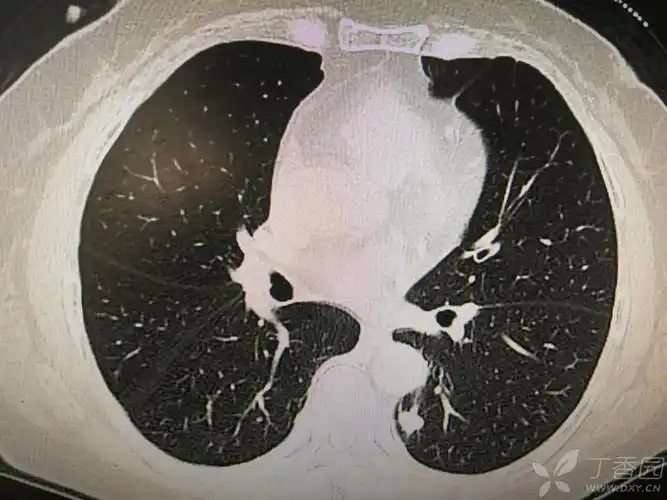

据影识病:双下肺分布的分叶状结节,肿瘤?结核?炎症? [病例帖]

左下肺背段见分叶状结节影,会是什么?